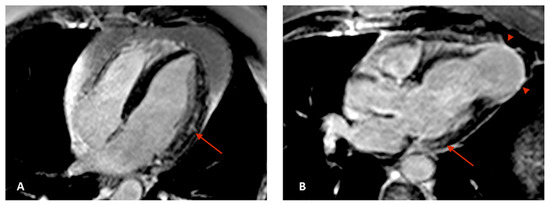

- Regueiro, A.; García-Álvarez, A.; Sitges, M.; Ortiz-Pérez, J.T.; De Caralt, M.T.; Pinazo, M.J.; Posada, E.; Heras, M.; Gascón, J.; Sanz, G. Myocardial involvement in Chagas disease: Insights from cardiac magnetic resonance. Int. J. Cardiol. 2013, 165, 107–112. [Google Scholar] [CrossRef]

- Mello, R.P.D.; Szarf, G.; Schvartzman, P.R.; Nakano, E.M.; Espinosa, M.M.; Szejnfeld, D.; Fernandes, V.; Lima, J.A.; Cirenza, C.; De Paola, A.A. Delayed enhancement cardiac magnetic resonance imaging can identify the risk for ventricular tachycardia in chronic Chagas’ heart disease. Arq. Bras. Cardiol. 2012, 98, 421–430. [Google Scholar] [CrossRef]

- Volpe, G.J.; Moreira, H.T.; Trad, H.S.; Wu, K.C.; Braggion-Santos, M.F.; Santos, M.K.; Maciel, B.C.; Pazin-Filho, A.; Marin-Neto, J.A.; Lima, J.A. Left ventricular scar and prognosis in chronic chagas cardiomyopathy. J. Am. Coll. Cardiol. 2018, 72, 2567–2576. [Google Scholar] [CrossRef]

- Torreão, J.A.; Ianni, B.M.; Mady, C.; Naia, E.; Rassi, C.H.; Nomura, C.; Parga, J.R.; Avila, L.F.; Ramires, J.A.; Kalil-Filho, R. Myocardial tissue characterization in Chagas’ heart disease by cardiovascular magnetic resonance. J. Cardiovasc. Magn. Reson. 2015, 17, 97. [Google Scholar] [CrossRef]